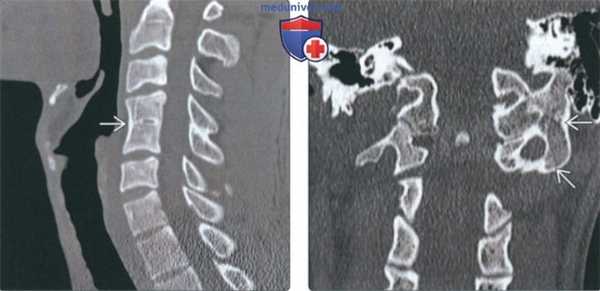

(Слева) На сагиттальной КТ (СКФ) определяется легкое нарушение сегментации на одном уровне (С4-С5). Узкая «талия» рудиментарного диска и слияние остистых отростков типичны для этой патологии.

(Справа) На корональной КТ в костном окне определяется вариант нарушения сегментации в виде крупной, хорошо отграниченной коаной «перемычки с кортикальной пластинкой (околомыщелковый отросток), соединяющей сосцевидный отроаок с поперечным отростком С1.